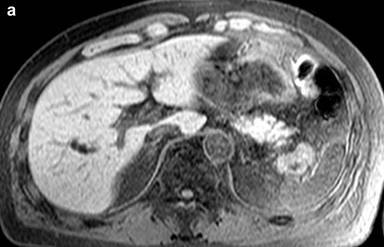

A 53-year-old man was incidentally found to have a cystic tumor in the tail of the pancreas after undergoing an abdominal ultrasound (US), which showed a 41x33 mm cystic mass in the pancreatic tail. He had no abdominal symptoms. The tumor markers, including DUPAN 2, and carbohydrate antigen 19-9, were within the normal ranges. The patient was referred to our hospital for further investigations. A contrast-enhanced CT scan (Figure 1) showed a non-enhanced cyst between the spleen and the pancreas with no solid component. Magnetic resonance cholangiopancreatography (Figure 2) revealed that the main pancreatic duct was regular and had no dilatation, and there was no communication between the cyst and the pancreatic duct. Magnetic resonance imaging (MRI) showed a lesion with a slightly high signal on a T1-weighted image; the lesion, which was well circumscribed, was in the tail of the pancreas (Figure 3). MRI on a T2-weighted image also showed the lesion with a high signal. The cystic tumor was negatively visualized on the PET image. Endoscopic ultrasound (EUS) was performed, which showed a 55x31 mm pancreatic tail lesion with a solid and cystic mixed component (Figure 4a). An endoscopic ultrasound-guided fine-needle aspiration biopsy in a trans-gastric approach of this lesion suggested a diagnosis of a benign squamous cyst (Figure 4b).

Figure 3. Abdominal magnetic resonance imaging findings. a. Slightly high intensity on a T1-weighted image. b. High intensity on a T2-weighted image. |